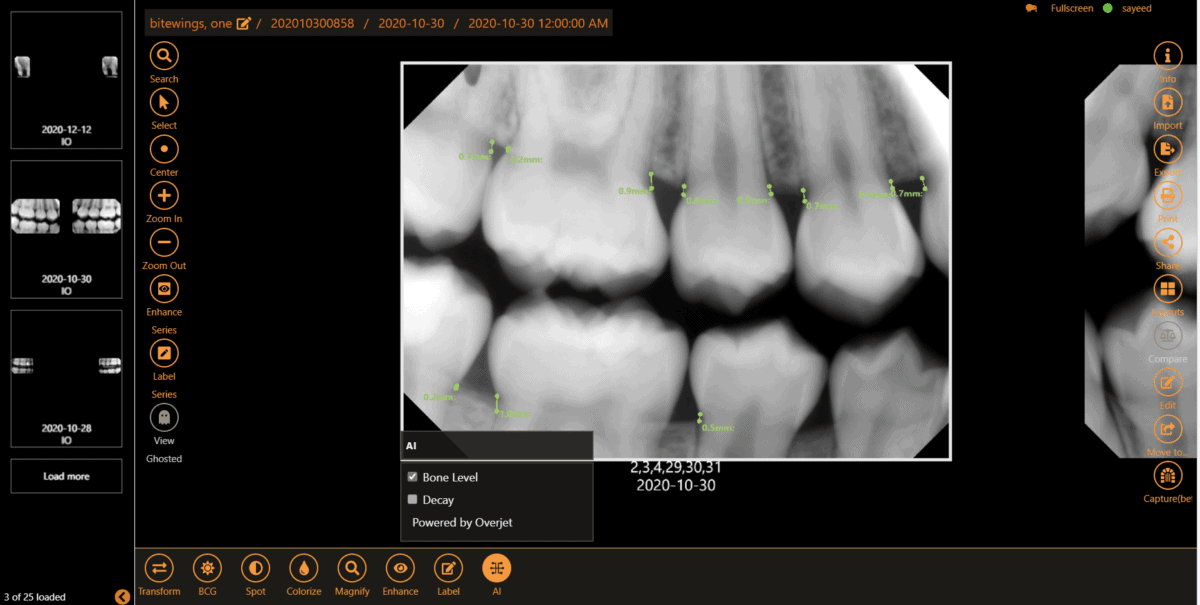

AI built into the dental imaging experience

Spot untreated issues sooner, get a second clinical perspective instantly, and show patients exactly what you see.

Improve diagnostic accuracy

Leverage custom clinical filters and image enhancement tools, templates, bitewings, and measurement tools. Quickly detect untreated conditions with AI analysis.